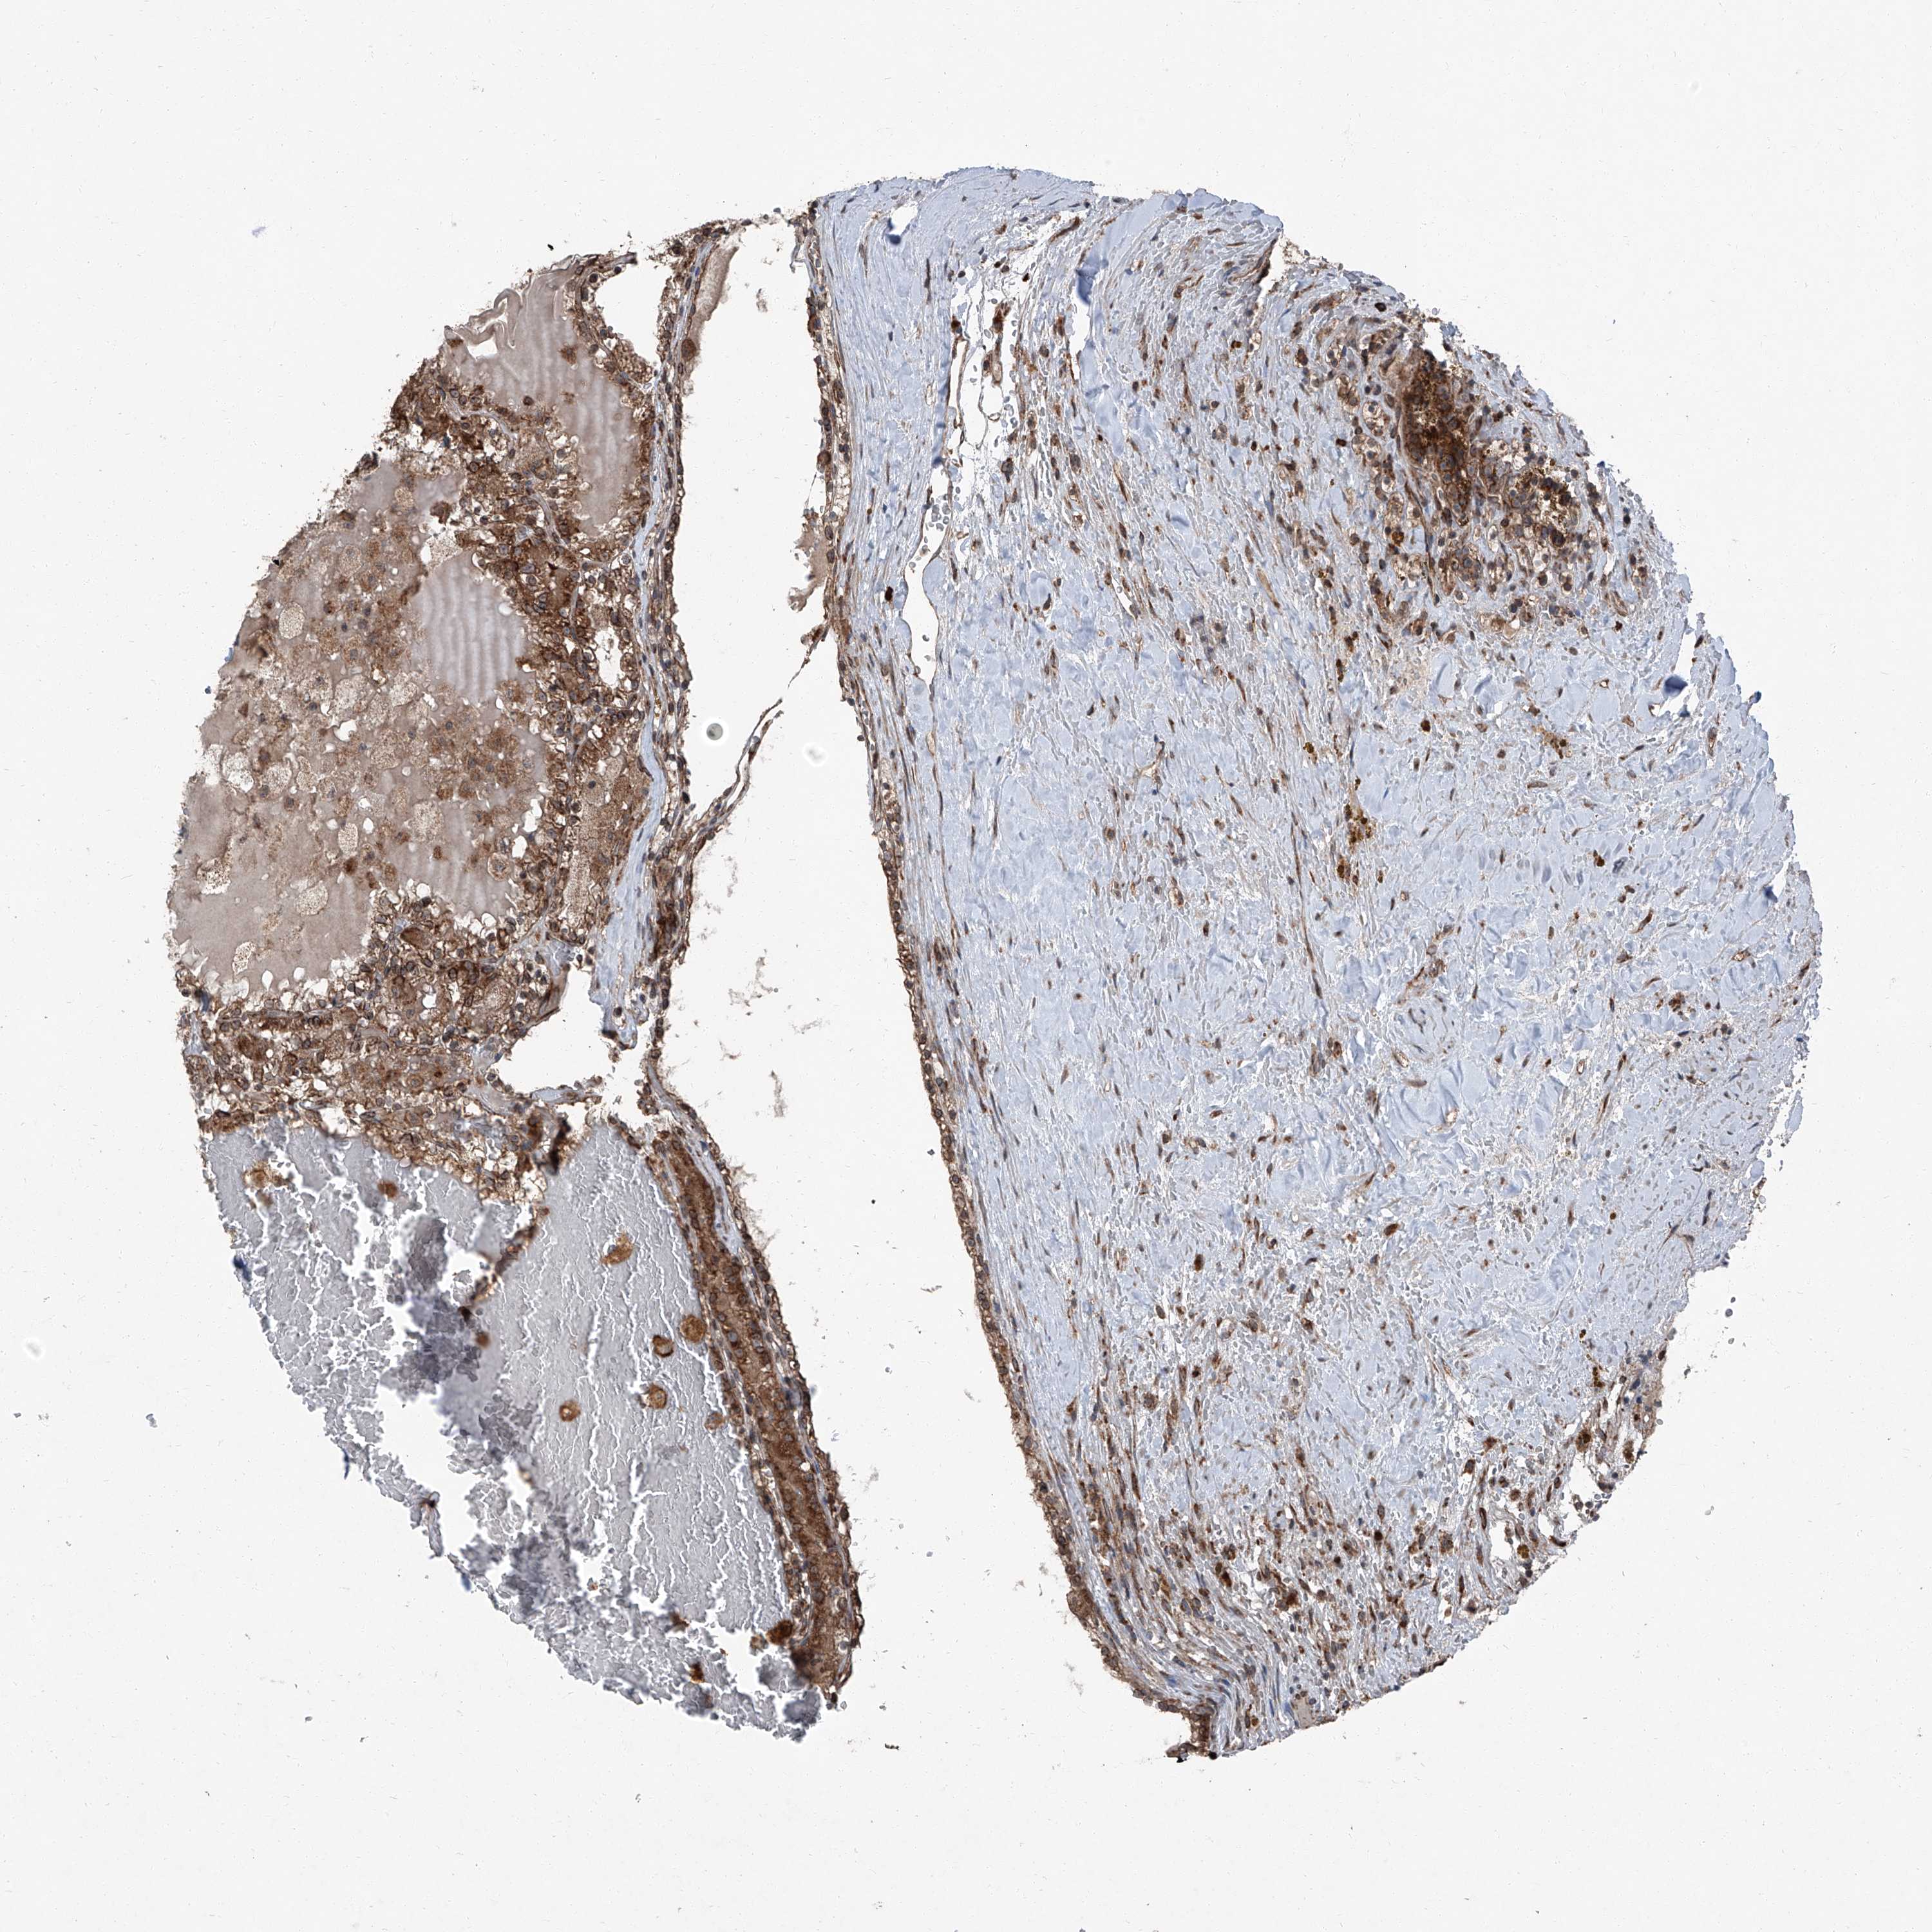

KIDNEY RENAL CLEAR CELL CARCINOMA (TCGA) - Interactive survival scatter ploti

The Survival Scatter plot shows the clinical status (i.e. dead or alive) for all individuals in the patient cohort, based on the same data that underlies the corresponding Kaplan-Meier plots. Patients that are alive at last time for follow-up are shown in blue and patients who have died during the study are shown in red.

The x-axis shows the expression levels (FPKM) of the investigated gene in the tumor tissue at the time of diagnosis. The y-axis shows the follow-up time after diagnosis (years). Both axes are complimented with kernel density curves demonstrating the data density over the axes. The top density plot shows the expression levels (FPKM) distribution among dead (red) and alive patients (blue). The right density plot shows the data density of the survived years of dead patients with high and low expression levels respectively, stratified using the cutoff indicated by the vertical dashed line through the Survival Scatter plot. This cutoff is automatically defined based on the FPKM cutoff that minimizes the p-score. The cutoff can be changed by dragging the vertical line or by entering a cutoff value in the square labeled "Current cut-off".

Under the Survival Scatter plot the p-score landscape (black curve; left axis) is shown together with dead median separation (red curve; right axis). Dead median separation is the difference in median mRNA expression between patients who have died with high and low expression, respectively. It is calculated as follows: median FPKM expression of dead patients with high expression - median FPKM expression of dead patients with low expression. This is intended to aid the user in visually exploring custom cutoffs and the associated p-scores and dead median separation.

Individual patient data is displayed and can be filtered by clicking on one or more of the category buttons on the top of the page. Categories describing expression level and patient information include: high, low, alive, dead, female, male and tumor stages. The scale of the x-axis can be toggled between linear and log-scale by clicking on the "x log" button. Mouse-over function shows TCGA ID, patient information and mRNA expression (FPKM) for each patient.

& Survival analysisi

Kaplan-Meier plots summarize results from analysis of correlation between mRNA expression level and patient survival. Patients were divided based on level of expression into one of the two groups "low" (under cut off) or "high" (over cut off). X-axis shows time for survival (years) and y-axis shows the probability of survival, where 1.0 corresponds to 100 percent.

LIMK1 is potential prognostic, high expression is unfavorable in Kidney Renal Clear Cell Carcinoma (TCGA)

Best expression cut offi

Based on the FPKM value of each gene, patients were classified into two groups and association between prognosis (survival) and gene expression (FPKM) was examined. The best expression cut-off refers the FPKM value that yields maximal difference with regard to survival between the two groups at the lowest log-rank P-value. Best expression cut-off was selected based on survival analysis .

When clicking on this number, the vertical dashed line indicating cut-off, the interactive survival plot, and the Kaplan-Meier curve will be adjusted to show results based on the best expression cut-off.

: 17.69

TCGA RNA samplesi

RNA-seq data is reported as average FPKM (number Fragments Per Kilobase of exon per Million reads), generated by the The Cancer Genome Atlas (TCGA) .

Normal distribution across the dataset is visualized with box plots, shown as median and 25th and 75th percentiles. Points are displayed as outliers if they are above or below 1.5 times the interquartile range. FPKM values of the individual samples are presented next to the box plot.

Average pTPM 15.9

Number of samples 521